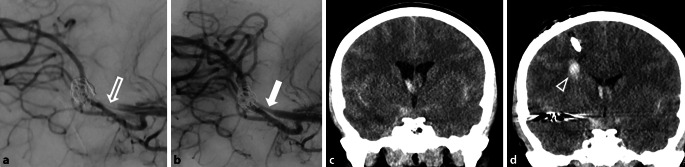

背景:蒂罗非班可用于治疗动脉瘤血栓栓塞并发症,也可用于动脉瘤治疗范围内所需的急性支架植入或血流分流器植入。我们旨在研究替罗非班在这类患者中的疗效和安全性:我们对 2009 年至 2019 年期间在我院接受动脉瘤治疗并接受围介入期替罗非班给药的所有患者进行了回顾性分析:共纳入 105 名患者,其中女性占 61%,男性占 39%(平均年龄 = 53 岁,IQR:44-60 岁)。67名患者接受了动脉瘤急诊治疗,38名患者接受了择期治疗。在接受急诊治疗的患者中,22%(15/67)发生了出血事件,7.46%(5/67)出现了症状。接受选择性动脉瘤治疗的患者没有发生出血事件(P = 0.002)。在35名需要脑室外引流管(EVD)的患者中,22.86%(8/35)的患者出现了与EVD相关的出血,但无一出现症状(p = 0.007)。在5名需要开颅手术的患者中,2人出现了严重出血,1人出现了非严重的开颅手术相关出血(p = 0.20):结论:在动脉瘤治疗的围介入并发症或紧急支架植入术中使用替罗非班可能是安全的。结论:在动脉瘤治疗的围介入并发症或急诊支架治疗中使用替罗非班可能是安全的,但在需要进行开颅手术时必须谨慎。在选择性动脉瘤治疗中,针对围手术期并发症使用替罗非班似乎是安全的。

Results: A total of 105 patients were included, with 61% women and 39% men (mean age = 53 years, IQR: 44-60 years). Sixty-seven patients underwent emergency aneurysm treatment, and thirty-eight were treated electively. Hemorrhagic events occurred in 22% (15/67) of the patients treated acutely, with 7.46% (5/67) exhibiting symptoms. Patients undergoing elective aneurysm treatment experienced no hemorrhagic events (p = 0.002). Among the 35 patients who required an external ventricular drain (EVD), 22.86% (8/35) developed EVD-related hemorrhages; however, none were symptomatic (p = 0.007). Of the five patients who required a craniotomy, two experienced significant bleeding, and one experienced non-significant craniotomy-related bleeding (p = 0.20).